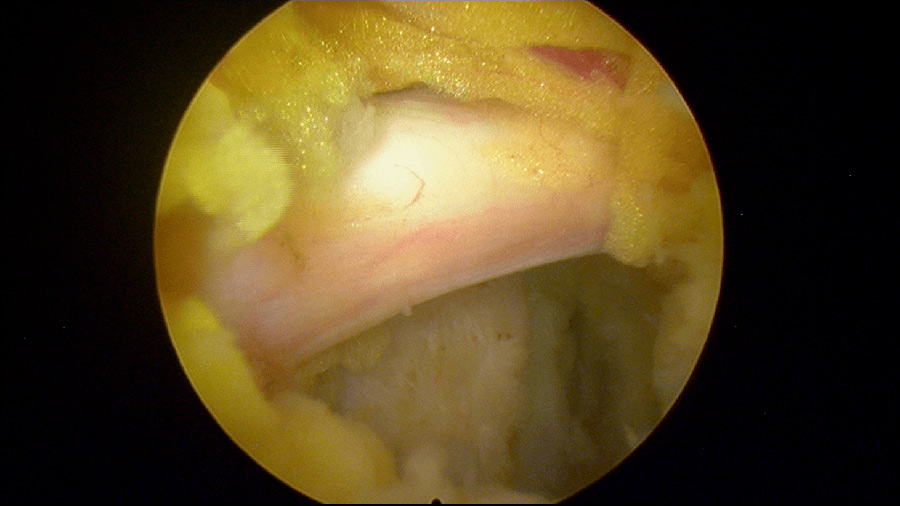

Caso clínico: endoscopia de columna multinivel L4L5 y L5S1

Durante la intervención quirúrgica, se abordarán los dos niveles mediante la técnica de endoscopia de columna.